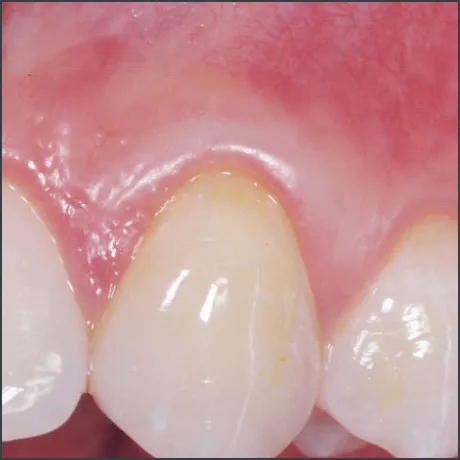

8 months after treatment with Straumann® Emdogain®.

Courtesy of Prof. Giovanni Zucchelli